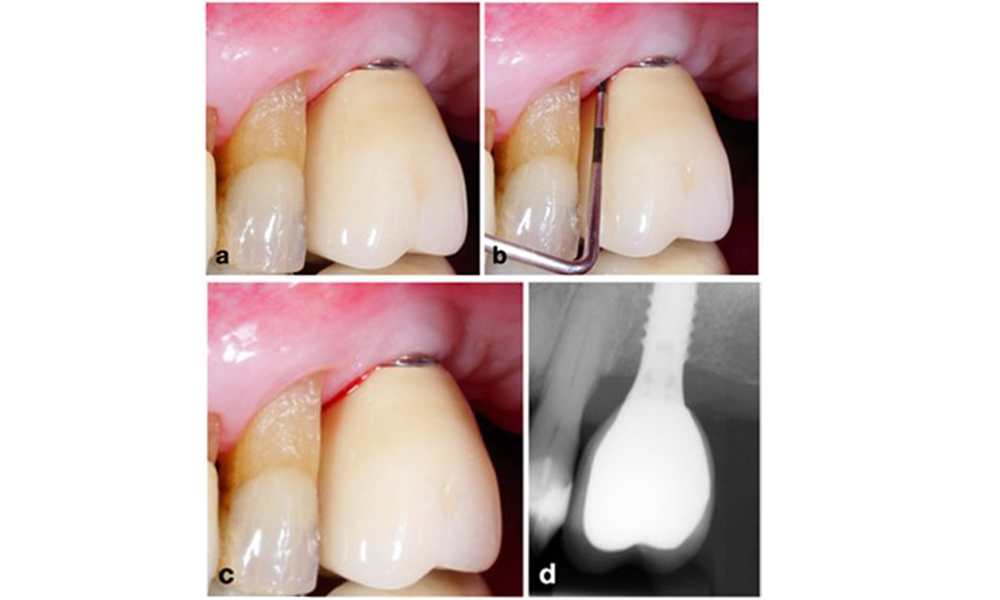

Abschließend bleibt anzumerken, dass Implantate mit weniger als 2 mm keratinierter Schleimhaut Beobachtungen zufolge eine erhöhte Prävalenz von Periimplantitis, eine stärkere Plaquebildung und einen höheren Blutungsindex aufweisen (Ramanauskaite et al. 2022). Dies unterstreicht, dass bei der Prävention und dem Management von Periimplantitis unbedingt eine Augmentation der keratinierten Schleimhaut in Erwägung gezogen werden sollte (Abb. 14).

Implantat mit zu wenig keratinierter Schleimhaut an der bukkalen Seite (a). Zur Verbreiterung der keratinisierten Schleimhaut wurde ein Gingivatransplantat eingesetzt (b), was eine wirksamere Oralhygiene ermöglicht (c).

Abb. 14. Implantat mit zu wenig keratinierter Schleimhaut an der bukkalen Seite (a). Zur Verbreiterung der keratinisierten Schleimhaut wurde ein Gingivatransplantat eingesetzt (b), was eine wirksamere Oralhygiene ermöglicht (c).